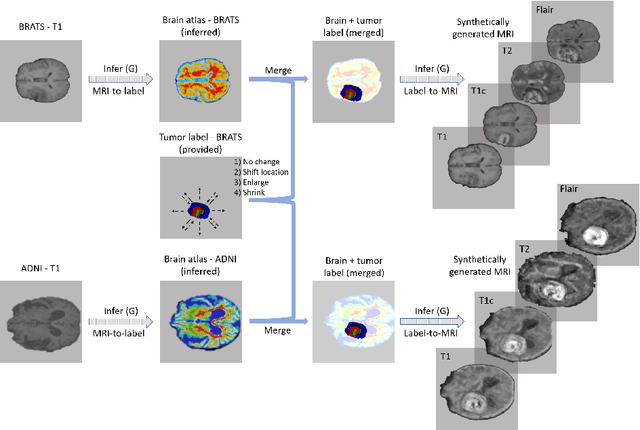

Data diversity is critical to success when training deep learning models. Medical imaging data sets are often imbalanced as pathologic findings are generally rare, which introduces significant challenges when training deep learning models. In this work, we propose a method to generate synthetic abnormal MRI images with brain tumors by training a generative adversarial network using two publicly available data sets of brain MRI. We demonstrate two unique benefits that the synthetic images provide. First, we illustrate improved performance on tumor segmentation by leveraging the synthetic images as a form of data augmentation. Second, we demonstrate the value of generative models as an anonymization tool, achieving comparable tumor segmentation results when trained on the synthetic data versus when trained on real subject data. Together, these results offer a potential solution to two of the largest challenges facing machine learning in medical imaging, namely the small incidence of pathological findings, and the restrictions around sharing of patient data.